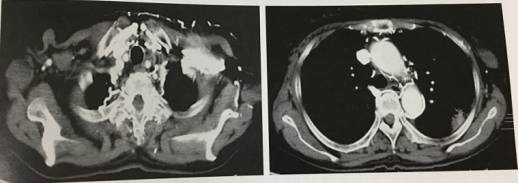

9、静脉内对比剂逆流

经上腔静脉属支高压对比剂,注射速度过快,导致对比剂逆流进入其他属支,显示胸壁及纵膈内多发线样明显强化的血管影,易误认为上腔静脉梗阻的侧支循环,增强连续层面显示上腔静脉通畅。